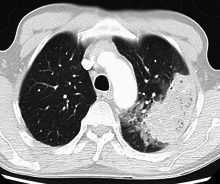

Pneumonia is typically diagnosed based on a combination of physical signs and a chest X-ray.[45] However, the underlying cause can be difficult to confirm, as there is no definitive test able to distinguish between bacterial and non-bacterial origin.[12][45] The World Health Organization has defined pneumonia in children clinically based on either a cough or difficulty breathing and a rapid respiratory rate, chest indrawing, or a decreased level of consciousness.[46] A rapid respiratory rate is defined as greater than 60 breaths per minute in children under 2 months old, 50 breaths per minute in children 2 months to 1 year old, or greater than 40 breaths per minute in children 1 to 5 years old.[46] In children, increased respiratory rate and lower chest indrawing are more sensitive than hearing chest crackles with a stethoscope.[19] Grunting and nasal flaring may be other useful signs in children less than five.[47]

In general, in adults, investigations are not needed in mild cases.[48] There is a very low risk of pneumonia if all vital signs and auscultation are normal.[49] In persons requiring hospitalization, pulse oximetry, chest radiography and blood tests—including a complete blood count, serum electrolytes, C-reactive protein level, and possibly liver function tests—are recommended.[48] The diagnosis of influenza-like illness can be made based on the signs and symptoms; however, confirmation of an influenza infection requires testing.[50] Thus, treatment is frequently based on the presence of influenza in the community or a rapid influenza test.[50]

Imaging

A chest radiograph is frequently used in diagnosis.[19] In people with mild disease, imaging is needed only in those with potential complications, those not having improved with treatment, or those in which the cause is uncertain.[19][48] If a person is sufficiently sick to require hospitalization, a chest radiograph is recommended.[48] Findings do not always match the severity of disease and do not reliably separate between bacterial infection and viral infection.[19]

X-ray presentations of pneumonia may be classified as lobar pneumonia, bronchopneumonia (also known as lobular pneumonia), and interstitial pneumonia.[51] Bacterial, community-acquired pneumonia classically show lung consolidation of one lung segmental lobe, which is known as lobar pneumonia.[29] However, findings may vary, and other patterns are common in other types of pneumonia.[29] Aspiration pneumonia may present with bilateral opacities primarily in the bases of the lungs and on the right side.[29] Radiographs of viral pneumonia may appear normal, appear hyper-inflated, have bilateral patchy areas, or present similar to bacterial pneumonia with lobar consolidation.[29] Radiologic findings may not be present in the early stages of the disease, especially in the presence of dehydration, or may be difficult to be interpreted in the obese or those with a history of lung disease.[20] A CT scan can give additional information in indeterminate cases.[29]

With treatment, most types of bacterial pneumonia will stabilize in 3–6 days.[87] It often takes a few weeks before most symptoms resolve.[87] X-ray finding typically clear within four weeks and mortality is low (less than 1%).[20][88] In the elderly or people with other lung problems, recovery may take more than 12 weeks. In persons requiring hospitalization, mortality may be as high as 10%, and in those requiring intensive care it may reach 30–50%.[20] Pneumonia is the most common hospital-acquired infection that causes death.[24] Before the advent of antibiotics, mortality was typically 30% in those that were hospitalized.[16]

In rare circumstances, bacteria in the lung will form a pocket of infected fluid called a lung abscess.[90] Lung abscesses can usually be seen with a chest X-ray but frequently require a chest CT scan to confirm the diagnosis.[90] Abscesses typically occur in aspiration pneumonia, and often contain several types of bacteria. Long-term antibiotics are usually adequate to treat a lung abscess, but sometimes the abscess must be drained by a surgeon or radiologist.[90]